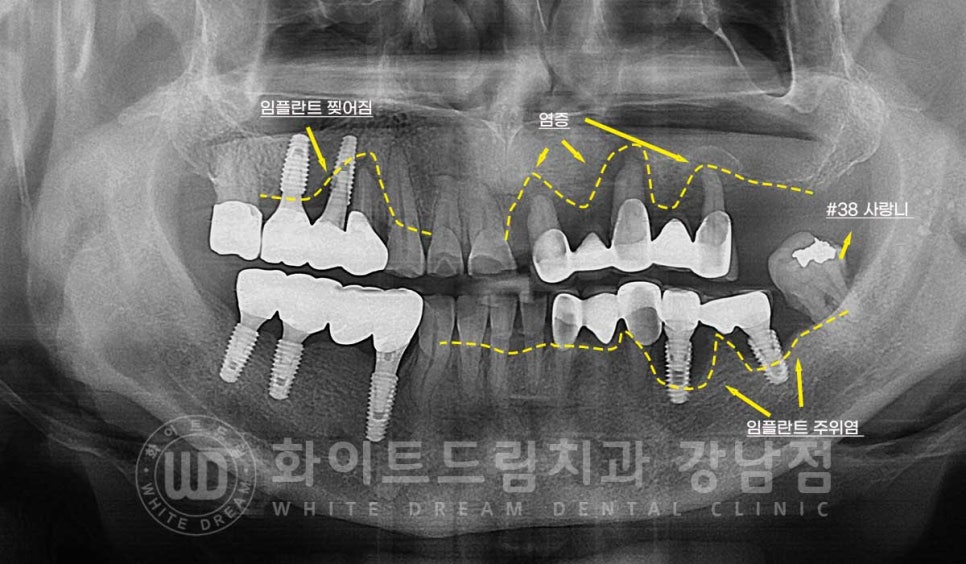

환자분의 초진 구내 사진입니다.

현재 임플란트가 식립되어 있는 10번대 어금니, 30번대 어금니 부위에

심한 염증과 골소실이 일어나 있는 상태입니다.

이 외에도 치주염으로 20번대 브릿지 부위의 상태도 굉장히 좋지 못한 상태인데

임플란트의 상태부터 자세히 보겠습니다.

임플란트 재수술의 주원인 / 찢어짐 & 주위염

10번대 어금니 부위는 임플란트가 찢어지면서 주위 염증이 생겨있고

40번대 어금니는 임플란트 주위염으로

증상은 모두 '임플란트 흔들림'이 발생하고 있는데요.